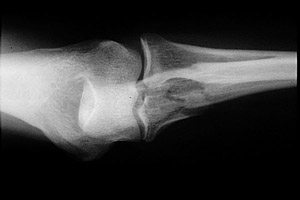

Monteggia fracture-dislocations are classified by the Bado system. Bado type I injuries are characterized by a proximal ulnar fracture with anterior dislocation of the radial head. This is due to a forceful pronation injury of the forearm and is the most common type. Bado type II injuries are "reversed" Monteggia fracture-dislocation injuries. Here, there is posterior angulation of the ulnar fracture site and posterior dislocation of the radial head. Bade type III and IV injuries are rare.

- Click on the image for a larger versionBLateral radiograph of the elbow. This demonstrates posterior dislocation of the radial head, a "reversed" Monteggia injury (Bado type II).